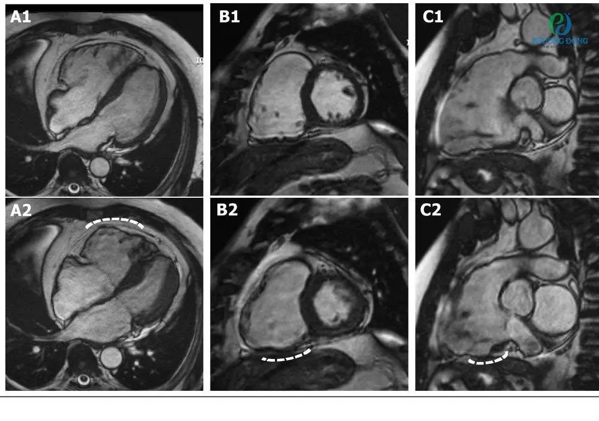

Chức năng tim

Hình 15. Hình ảnh MRI tim

Khớp gối: Nhiều chuỗi xung 3D cho độ phân giải rất cao, hiển thị sụn viền rõ cùng nhiều chương trình giúp đánh giá thoái khớp khớp sớm